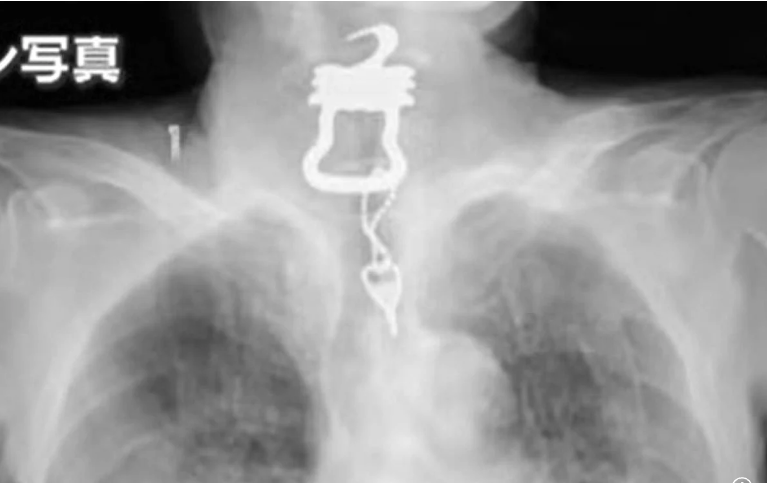

ونُقل كينيتشي أونيشي، 82 عامًا، إلى مستشفى أوساكا في يناير 2022 بعد كسر عظمة صدره إثر سقوطه. وبعد بضعة أشهر، في سبتمبر، اشتكى من ألم في الحلق وشُخِّصت إصابته بفيروس كوفيد-19. ومع ذلك، أظهرت الأشعة السينية على الصدر ظلًا كبيرًا في حلقه، والذي تم تحديده لاحقًا على أنه مفتاح بطول 12 سم متصل بسلسلة مفاتيح.

وقال ابنه البالغ من العمر 55 عامًا، وفقًا لقناة "يوميوري": "في البداية، تخيلت أنه مفتاح صغير ابتلعه عن طريق الخطأ". لكن عندما رأيته، صُدمتُ. كان ثقيلًا وشكله غريبًا." وأوضح "كان المفتاح المعدني، مع سلسلة على شكل أوزة ذات حواف حادة" وهو كما تبين مفتاح ملابس يُستخدم لتأمين بذلة خاصة مصممة لمنع المرضى من العبث بالمعدات الطبية أو الحفاضات، وكان والده، الذي شُخِّص بالخرف الخفيف، يرتدي البدلة أثناء إقامته.